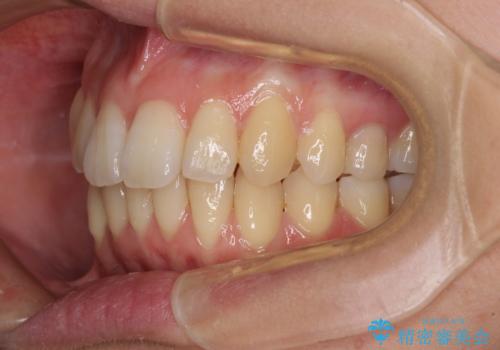

突出した印象のあった前歯をきれいに引っ込めることができたので、口が閉じやすくなり、横顔の印象をスッキリとさせることができました。

でこぼこしていて磨きにくかった歯と歯の間も清掃しやすくなり、患者様には大変満足していただきました。